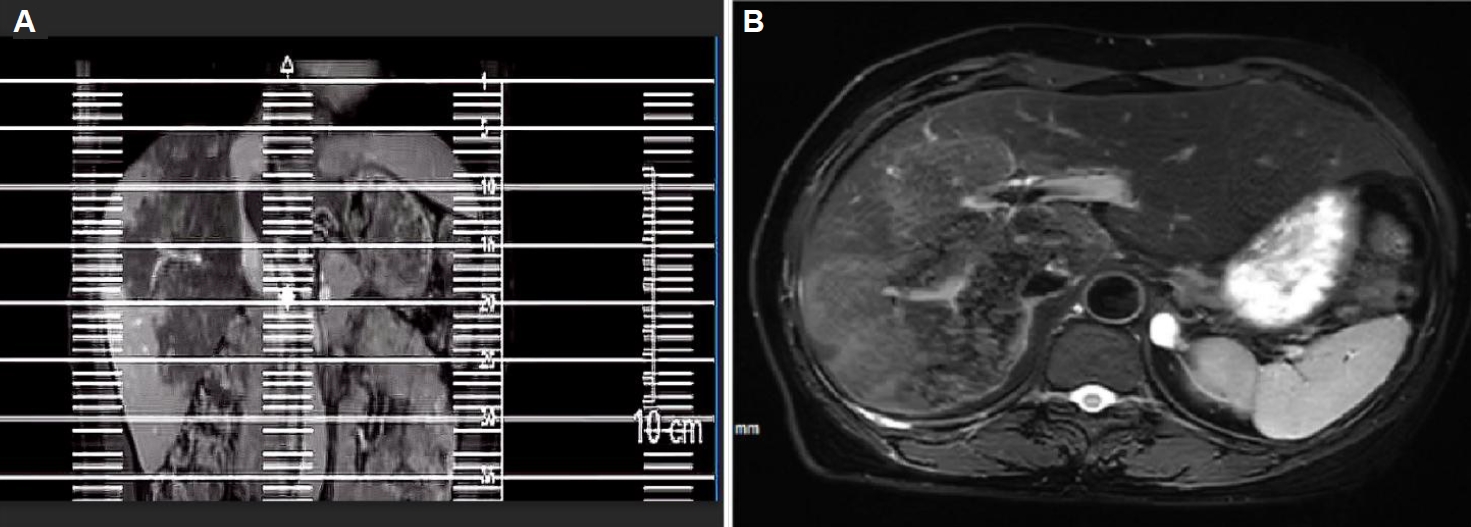

Ultrasound showed a heterogeneous hyperechoic mass (7.8×5.5 cm) with unclear borders in liver segments S4, S7, and S8 (Fig. 1). Computed tomography suggested a large, poorly defined mass with mixed density and patchy calcifications (maximum cross-sectional area 15.11×11.29 cm) in the liver. No enhancement was observed in dynamic contrast imaging. A low-density lesion in the left adrenal gland showed no enhancement (Fig. 2A). The right portal vein was narrowed. The right and middle hepatic veins were partially obscured in the portal venous phase (Fig. 2B). The presence of a large, infiltrative mass with heterogeneous density and irregular calcifications is a recognized, though not universal, imaging presentation of advanced alveolar echinococcosis, which can mimic malignancy.

Magnetic resonance imaging showed irregular, slightly hyperintense T1 signals in the right lobe and caudate lobe (14.5×9.6×11.5 cm) without enhancement. The capsule showed enhancement, with inferior vena cava locally compressed. Diffusion-weighted imaging revealed slightly high signals (Fig. 3). T2-weighted imaging showed irregular, slightly hyperintense T2 signals in the right lobe and caudate lobe, with high diffusion-weighted imaging signals. A round, hyperintense T2 lesion (1.6×1.3 cm) was seen in the left adrenal gland (Fig. 4A, B). The absence of typical multilocular cystic structures cannot rule out HAE, as the disease may present as a solid, pseudotumoral mass with central necrosis and peripheral fibrosis, especially in endemic areas.

Fig. 2.

Abdominal computed tomography (CT) of the liver. (A) Arterial phase CT demonstrates a large hypodense occupying lesion in the liver with patchy hyperdense areas, showing no enhancement. A non-enhancing hypodense lesion is observed in the left adrenal region. (B) Portal venous phase CT reveals stenosis of the right portal vein branch within the lesion area, with partial obscuration of the right and middle hepatic veins.

Fig. 2. Abdominal computed tomography (CT) of the liver. (A) Arterial phase CT demonstrates a large hypodense occupying lesion in the liver with patchy hyperdense areas, showing no enhancement. A non-enhancing hypodense lesion is observed in the left adrenal region. (B) Portal venous phase CT reveals stenosis of the right portal vein branch within the lesion area, with partial obscuration of the right and middle hepatic veins.